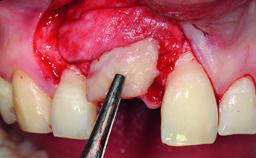

A 32-year-old female Caucasian patient with a compromised maxillary right central incisor was referred to us by a general dentist. Her chief complaints were discomfort and mobility of tooth 11 with unsatisfactory esthetics due to discoloration. The patient reported a previous trauma, some years earlier, as the origin of pathology on the afflicted tooth. Anamnesis was negative for any other dental or periodontal pathology in the remaining dentition. The patient did not take any medication and reported to be a light smoker (5–10 cigs/day). She had high esthetic expectations of her treatment. The extraoral examination revealed a high smile line with full exposure of her maxillary teeth and surrounding soft tissue in the area between the second premolars.

Bone Augmentation Horizontal|Simultaneous|Staged

Augmentation Materials Autogenous chips|Xenogenous|Membrane

Soft Tissue Grafting Staged